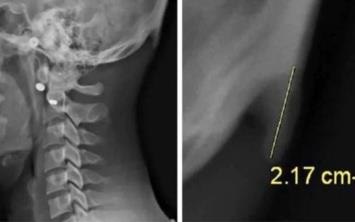

2. Avustralya’daki Sunshine Coast Üniversitesi’den bilim adamları Dr. David Shahar ve Prof. Mark Sayers, 18-30 yaş arasındaki 218 kişinin röntgen çekimlerini inceledi. Yapılan araştırmalar sonucu röntgen çekilen kişilerin neredeyse yarısının kafatası şeklinin yoğun cep telefonu ve tablet kullanımına bağlı olarak ‘değiştiği’, boynuzumsu bir çıkıntıya benzediği belirtildi.

Avustralya’daki Sunshine Coast Üniversitesi’den bilim adamları Dr. David Shahar ve Prof. Mark Sayers, 18-30 yaş arasındaki 218 kişinin röntgen çekimlerini inceledi. Yapılan araştırmalar sonucu röntgen çekilen kişilerin neredeyse yarısının kafatası şeklinin yoğun cep telefonu ve tablet kullanımına bağlı olarak ‘değiştiği’, boynuzumsu bir çıkıntıya benzediği belirtildi.

6. Ensenin üstünde sivrilen 10-30 milimetre arasında değişen çıkıntıya, &#8216;dış oksipital kabartı&#8217; deniyor. Dış oksipital kabartıya, taşınabilir dijital cihazlar yaygınlaşmaya başlamadan önce daha çok yaşlı insanlarda rastlandığı, gençlerde ise oldukça nadiren rastlandığı belirtiliyor.

Ensenin üstünde sivrilen 10-30 milimetre arasında değişen çıkıntıya, ‘dış oksipital kabartı’ deniyor. Dış oksipital kabartıya, taşınabilir dijital cihazlar yaygınlaşmaya başlamadan önce daha çok yaşlı insanlarda rastlandığı, gençlerde ise oldukça nadiren rastlandığı belirtiliyor.